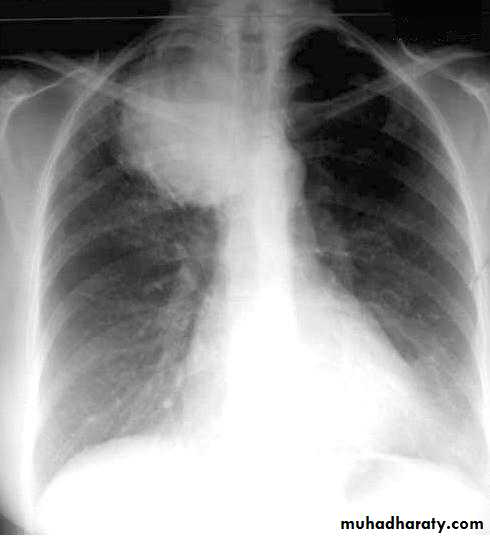

Pneumothorax

A: before treatmentB: after treatment